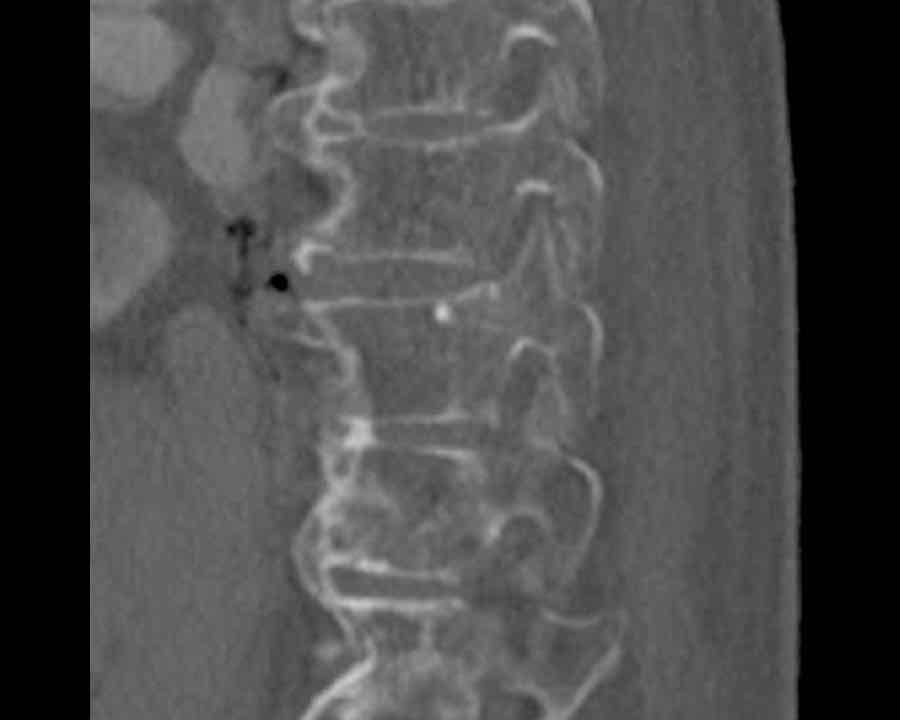

Scroll through images.

What are the findings?

Findings

- C injury? No.

- Signs of a rigid spine?

Yes, clear example of SpA so be aware of a B3 injury. - Horizontal fracture of vertebral body (white circle)

- Subtle separation anteriorly at the fracture level

Conclusion

injury type B3.